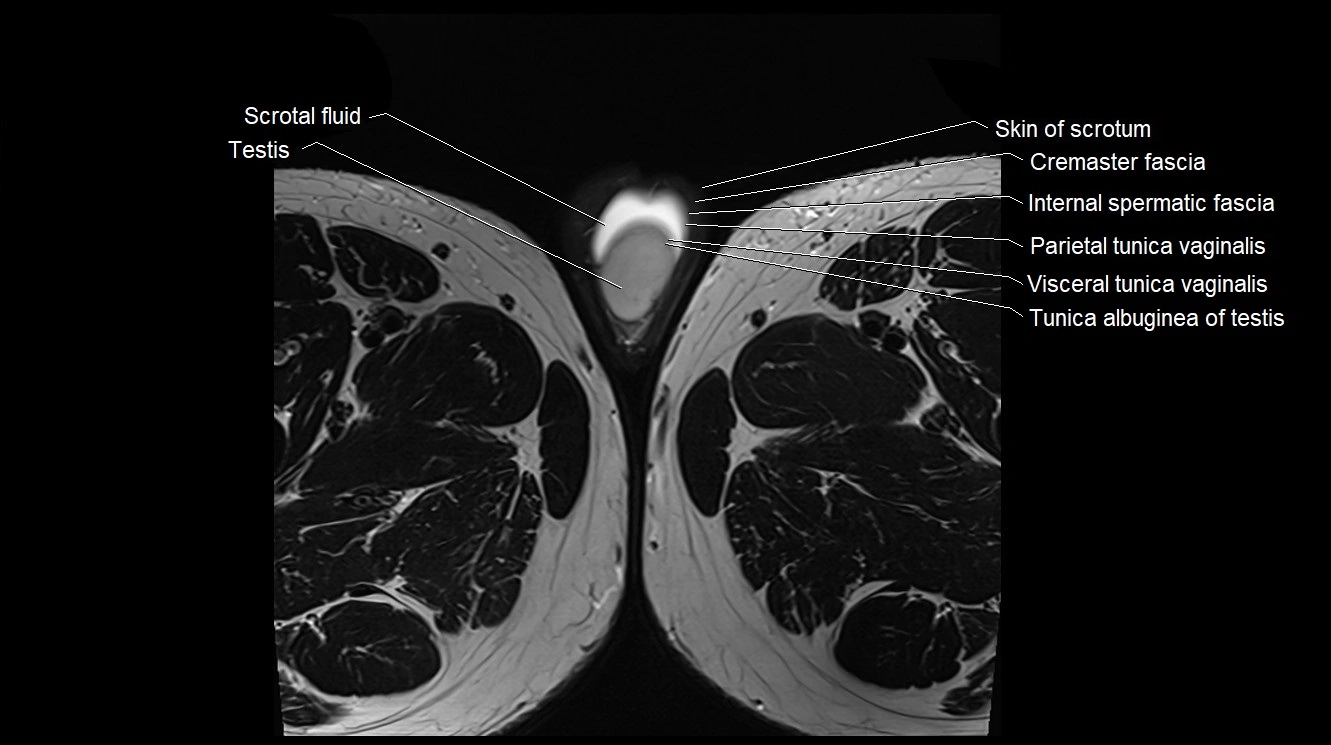

- Cremaster fascia

- Cremaster muscle

- Internal spermatic fascia

- Parietal tunica vaginalis

- Scrotal fluid

- Skin of scrotum

- Testis

- Tunica albuginea of testis

- Visceral tunica vaginalis